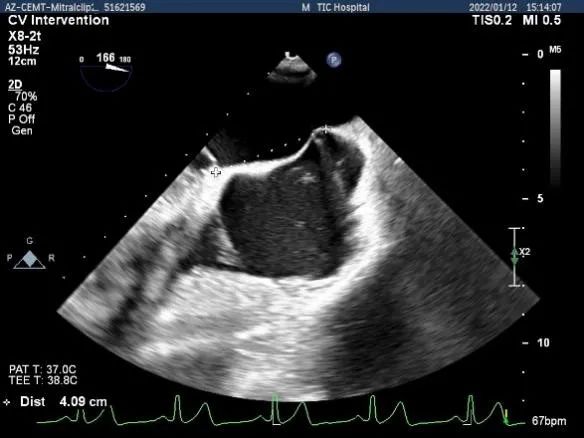

确定房间隔穿刺点:中部靠后

穿刺点高度测量:4.09cm,由于病变部位靠前交界,穿刺高度尚可